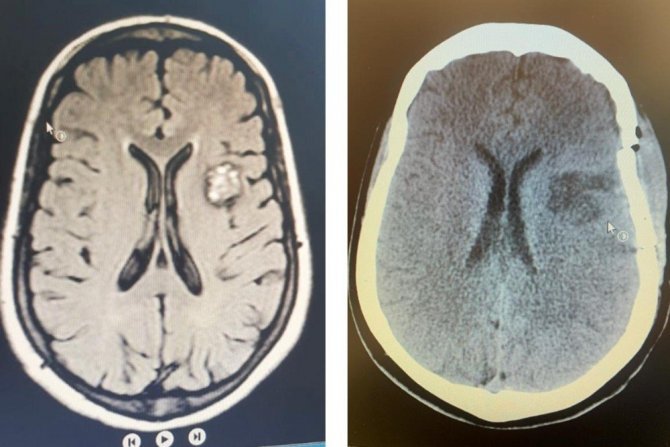

Диагностика

Метод визуализации, используемый в диагностике каверномы, — МРТ. В отличие от АВМ, при каверноме нет необходимости в цифровой церебральной ангиографии.